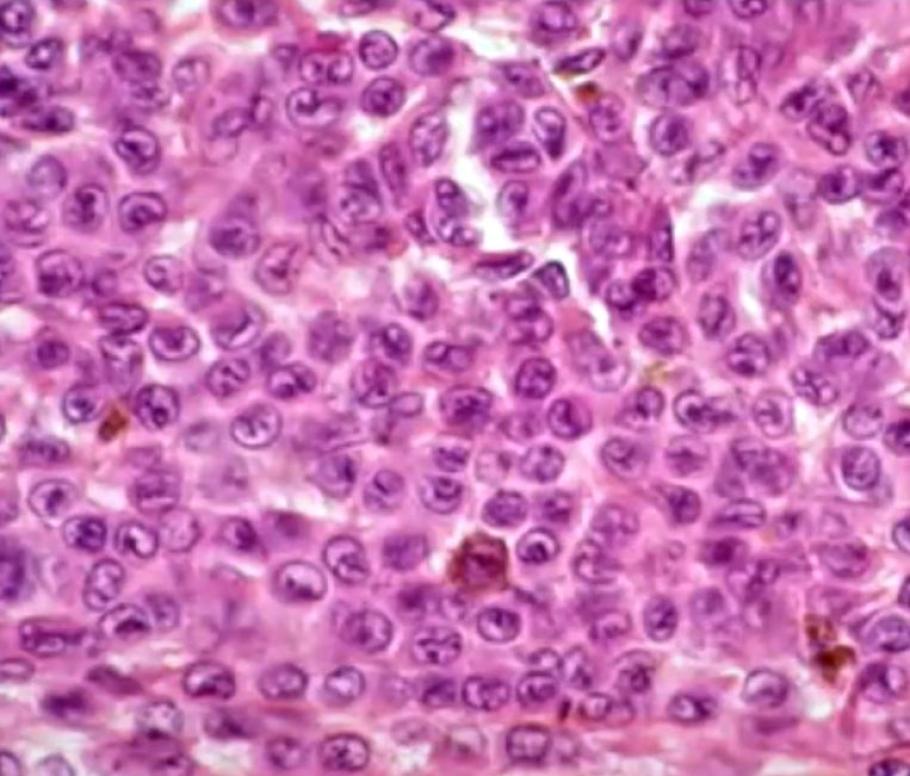

A travers ce challenge, les compétiteurs devaient développer des modèles d’apprentissage automatique capables de prédire la probabilité de récidive de mélanomes dans les cinq ans suivant le diagnostic initial. Pour relever ce défi, ils ont eu accès à une base de données multicentrique inédite, combinant données cliniques et lames d’histopathologie numérisées issues de près de 2 000 patients.

Au-delà du développement et de la publication d’algorithmes d’intelligence artificielle performants, ce data challenge a également permis de soutenir la création d’une base de données anonymisées unique et de grande qualité rassemblant près de 2 000 données cliniques associées aux données d’imagerie collectées dans 40 centres français.